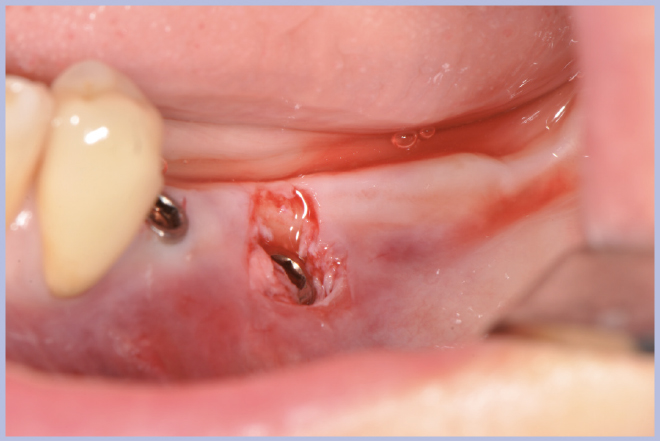

- Figg. 31-35 – Al momento della riapertura utilizzo della guida chirurgica per l’esposizione implantare

- Fig. 32